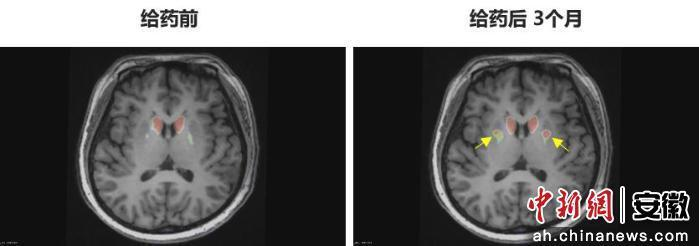

圖為李女士 PET-DAT/MRI融合圖像術前與術后三個月對比。

圖為李女士?PET-DAT/MRI融合圖像術前與術后三個月對比。

“身體不僵硬了,像正常人一樣?!崩钆啃χf。多年的抖動與“關期”徹底消失,她重新感受到身體的輕盈和心靈的自由。術后影像顯示,移植細胞已在腦內成功定植并發揮功能,醫生稱這些“亮點”是新生多巴胺能神經元的直接證據。